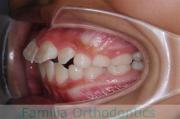

歯並びを治したいということで来院されました。下あごがやや右側に偏位して後退している、上顎前突(出っ歯)でした。上下左右から小臼歯を抜歯して、歯科矯正用アンカースクリューを併用したマルチブラケット法にて治療を行いました。約2年、24回の来院をしていただきました。

下顎の後退はいびきなどの上部気道の障害が出やすいと考えられます。

右側

正面

左側